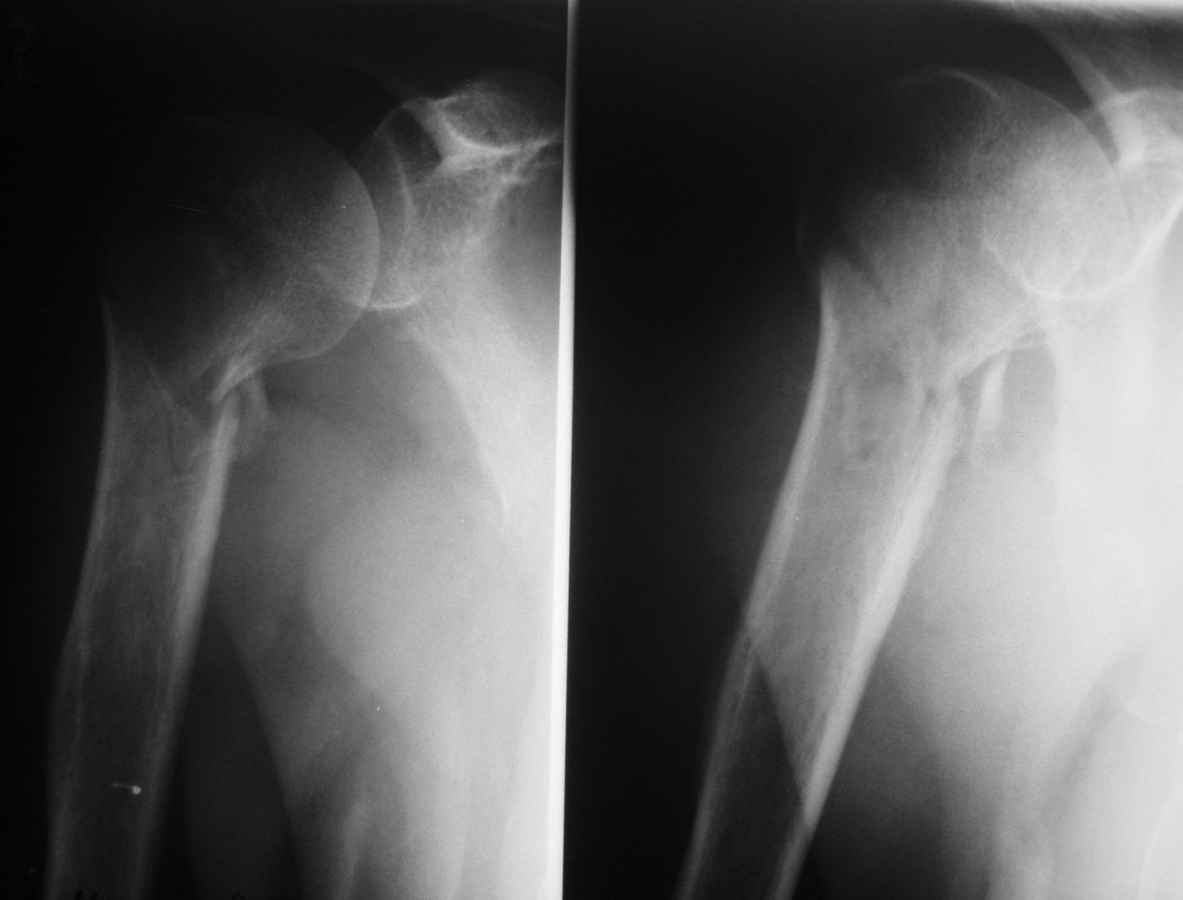

Пациент 55 лет. травма 7.07.09г (первая Р-грамма). Лечился консервативно, надолго выпадал из под наблюдения леч. врача. Последний снимок от 7.08.09 г. Как видно на Р-грамме, стояние отломков неудовлетворительное, клинически выраженная патологическая подвижность. Соп. дз: сахарный диабет 1 типа, средней тяжести.

Выскажите Ваше мнение о дальнейше тактике лечения данного пациента.